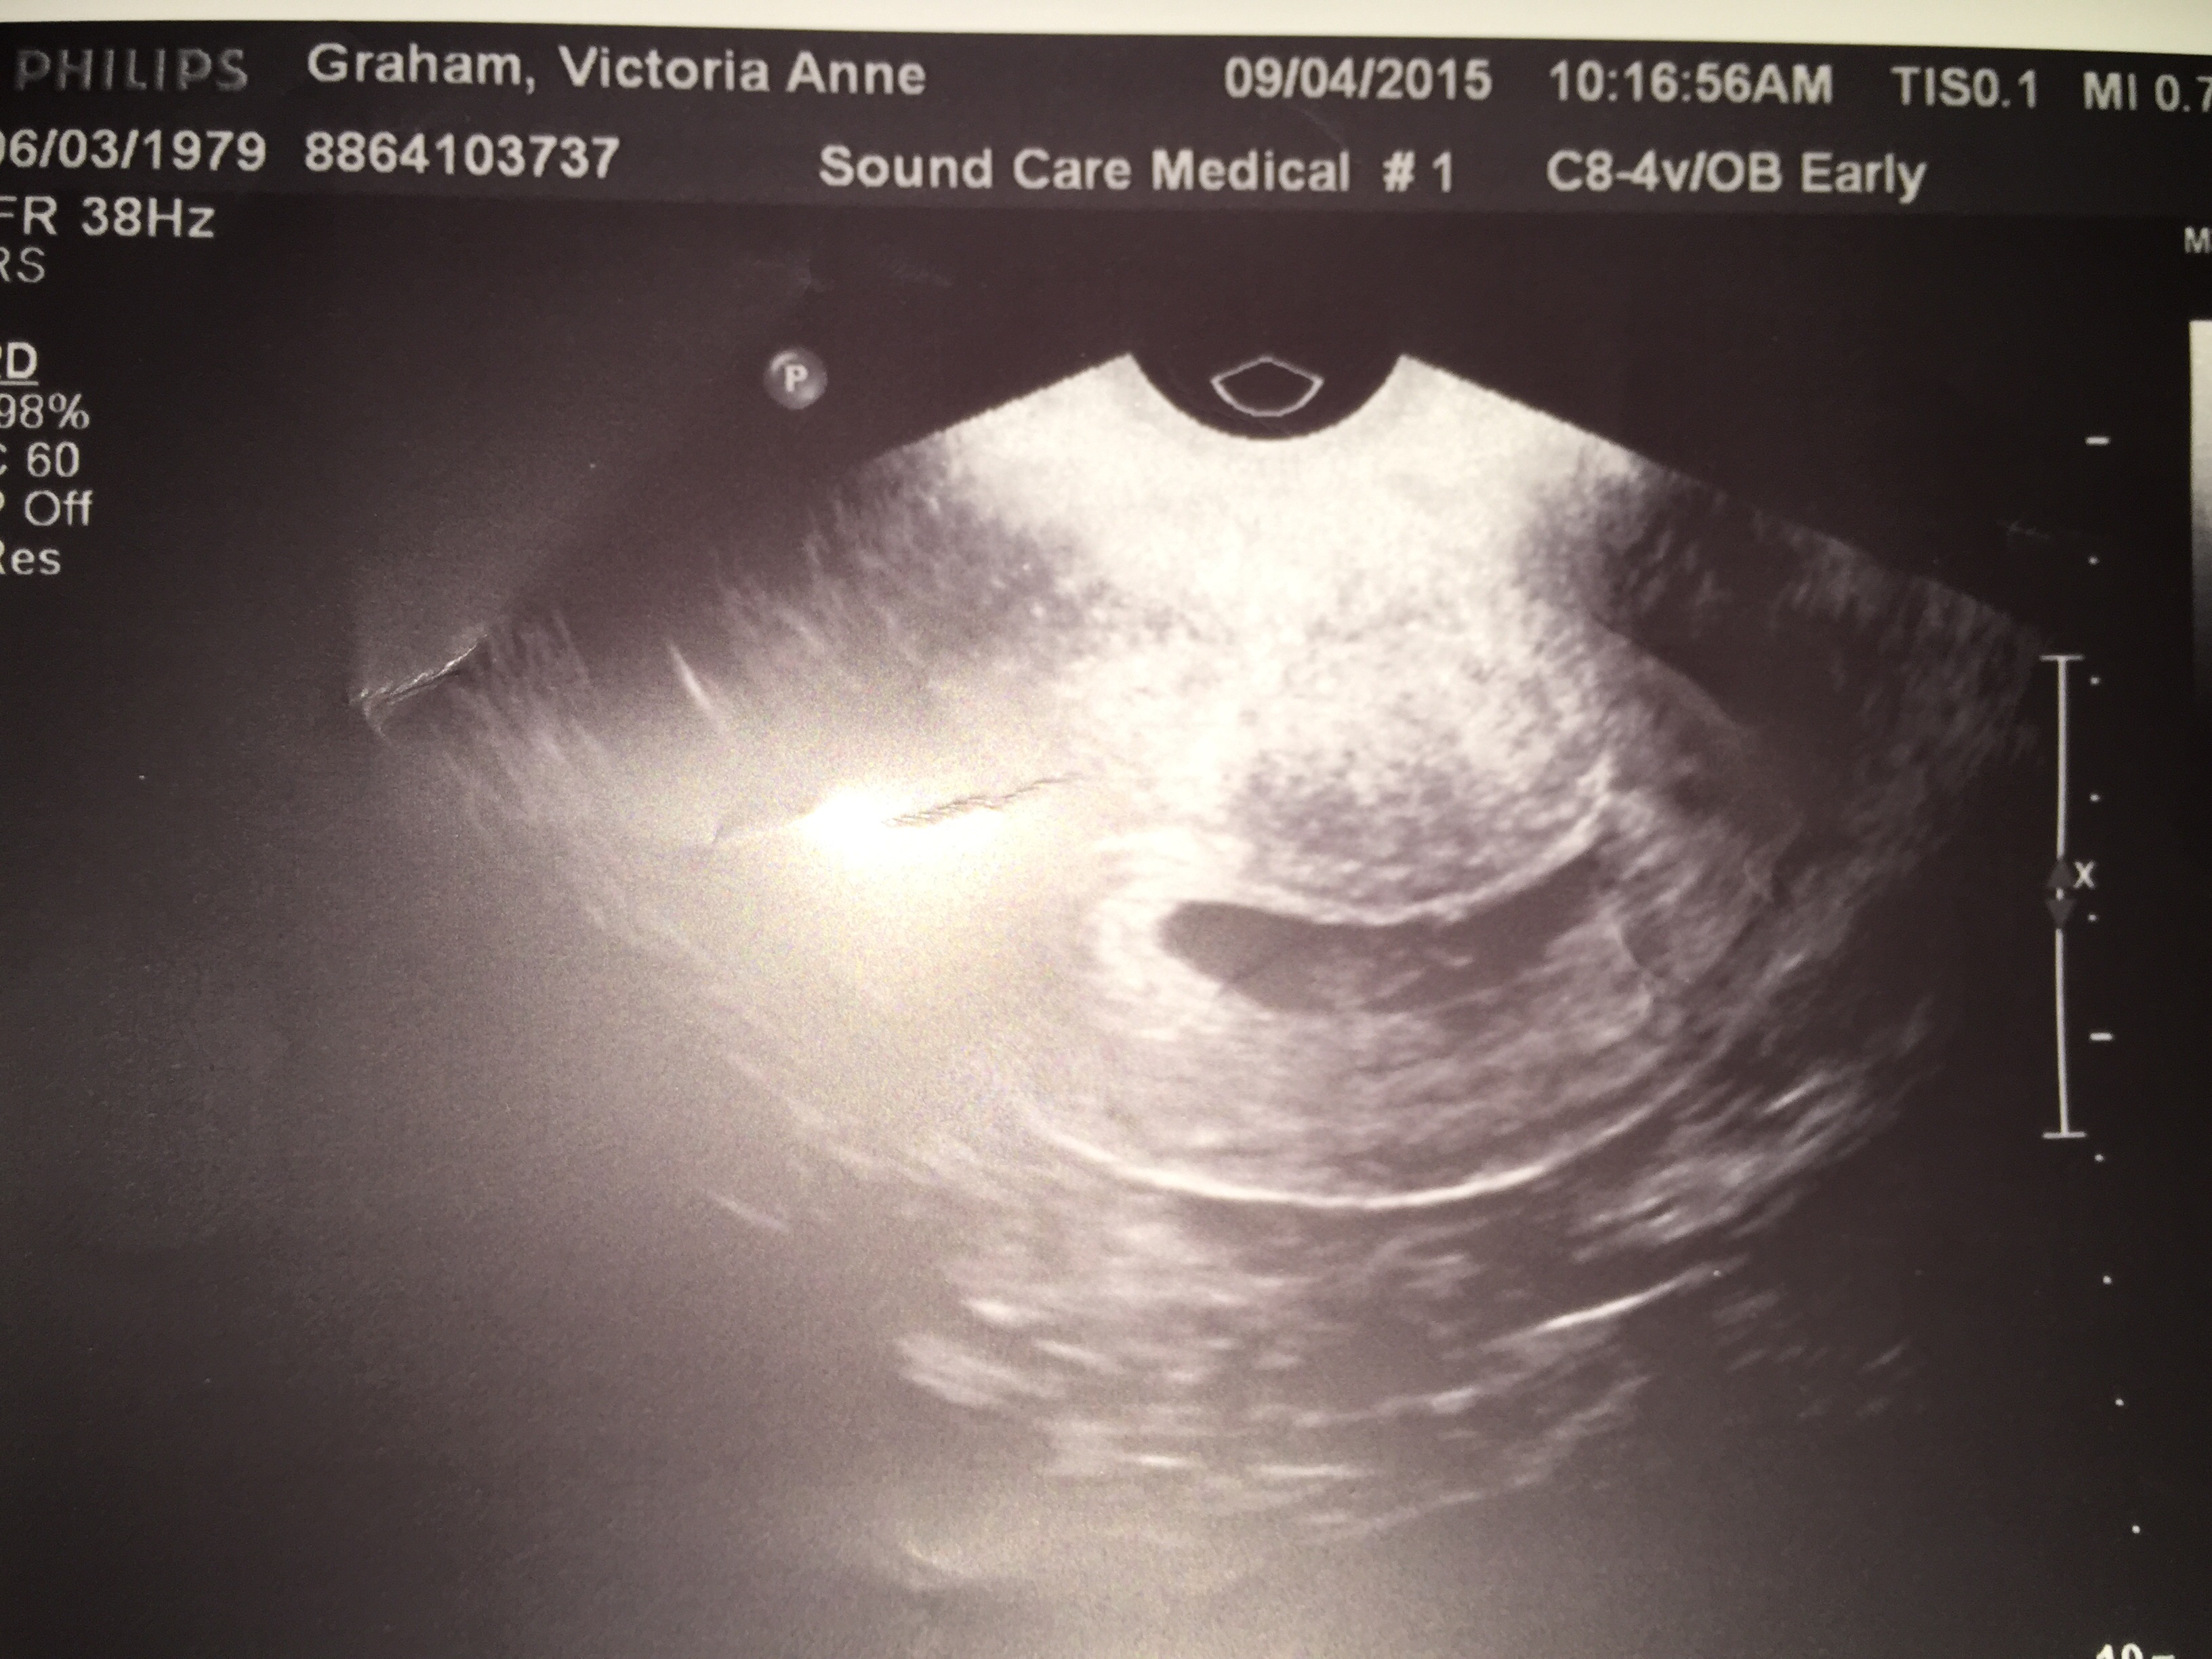

• I'm 10 weeks today. My due date is April 7th. This picture is actually from my second ultrasound that I got yesterday. I got my first one done at 7 weeks and 5 days due to some minor bleeding which they determined was from a small blood blister in my uterus. As of yesterday we got the good news that the blood blister has shrunk dramatically! So now my appointments will continue on as normal. The baby's heartbeat was 156 at my first appointment and yesterday it was 175. I'm not sure I can accurately describe how happy I was to see my little baby moving around on the screen yesterday! It's truly something magical.